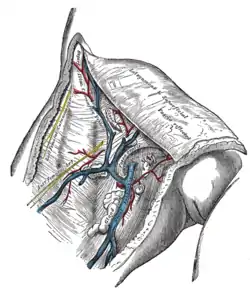

The great saphenous vein and its tributaries at the fossa ovalis in the groin. | |

Near the fossa ovalis it is joined by the superficial epigastric, superficial circumflex iliac vein, and superficial external pudendal veins.

The thoracoepigastric vein runs along the lateral aspect of the trunk between the superficial epigastric vein below and the lateral thoracic vein above and establishes an important communication between the femoral vein and the axillary vein.